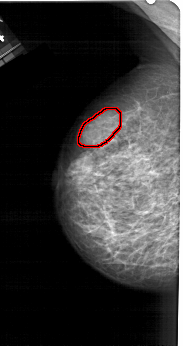

A_1279_1.LEFT_CC

LEFT_CC LINES 5146 PIXELS_PER_LINE 2731 BITS_PER_PIXEL 12 RESOLUTION 43.5 OVERLAY

FILE: A_1279_1.LEFT_CC.OVERLAY

TOTAL_ABNORMALITIES 1

ABNORMALITY 1

LESION_TYPE MASS SHAPE LOBULATED MARGINS CIRCUMSCRIBED

ASSESSMENT 4

SUBTLETY 2

PATHOLOGY BENIGN

TOTAL_OUTLINES 1

BOUNDARY